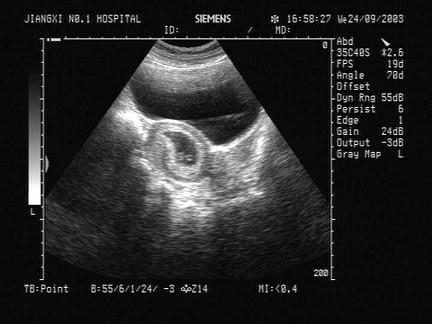

女性,32岁,停经45天,B超检查如图,最可能的诊断为?(?)A.宫腔积液B.宫体肌瘤C.早期妊娠D.子宫粘膜下肌瘤E.卵巢囊肿

问题 女性,32岁,停经45天,B超检查如图,最可能的诊断为?(?)

选项 A.宫腔积液 B.宫体肌瘤 C.早期妊娠 D.子宫粘膜下肌瘤 E.卵巢囊肿

答案 C